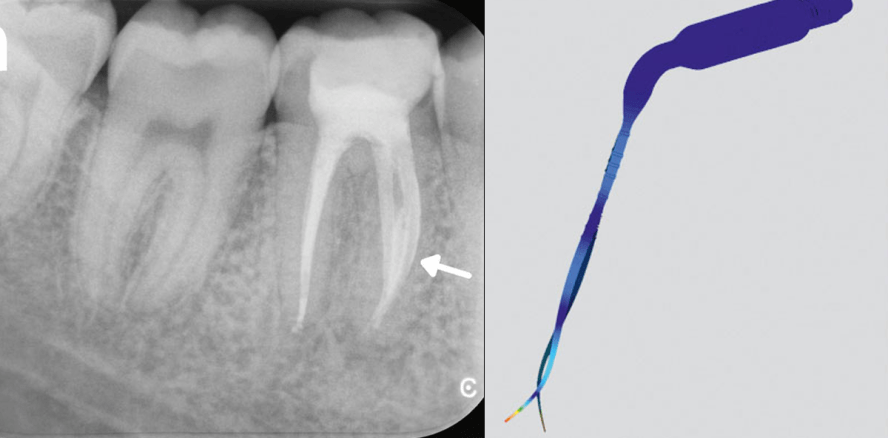

Das Self-Adusting-File (SAF) System ermöglicht einen neuen mikroinvasiven Ansatz in der Endodontie. Diesem Konzept zufolge kann eine bessere...

Das Self-Adusting-File (SAF) System ermöglicht einen neuen mikroinvasiven Ansatz in der...